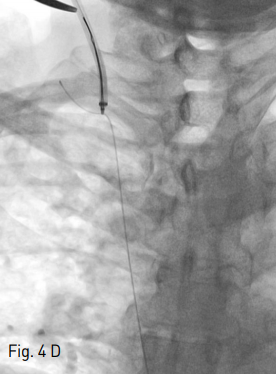

Fig 4D

A 0.035-inch guidewire was passed through the left hepatic vein, IVC, right atrium and SVC into the right innominate vein. Then transhepatic wire was snared using snare catheter providing through-and-through access (D).